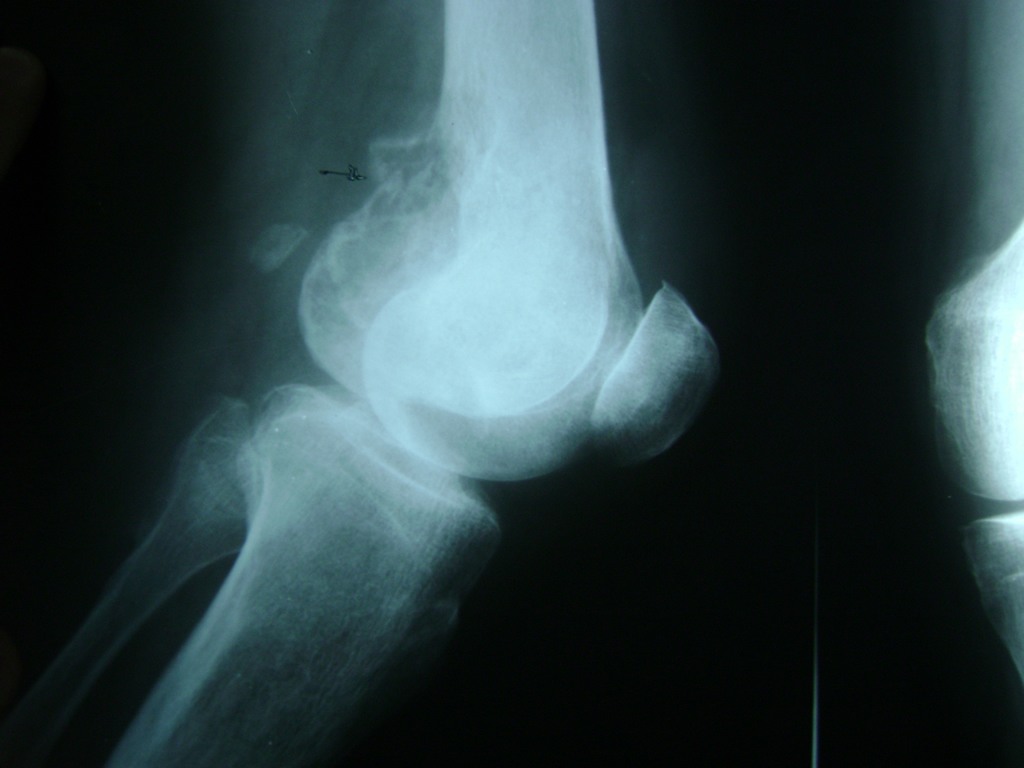

Cirugías de Húmero - Rodilla

La artroscopia de rodilla es un cirugía en el cual la estructura interna de la articulación es examinada ya sea para realizar un diagnostico o para realizar un tratamiento, este procedimiento se realiza utilizando un instrumento parecido a un pequeño tubo llamado artroscopio.